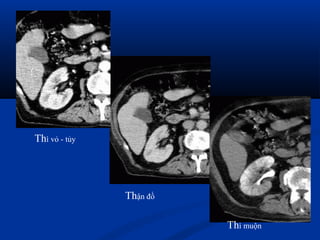

 CT :CT :

 Khảo sát hình thái và chức năngKhảo sát hình thái và chức năng

 KT nhạy nhất để tìm ổ nhiễm trùng : dùngKT nhạy nhất để tìm ổ nhiễm trùng : dùng

dynamic CT, có hình ảnh giữ thuốc cản quang tạidynamic CT, có hình ảnh giữ thuốc cản quang tại

thì muộn.thì muộn.

 Dấu hiệu gián tiếp: đường bờ mờ, dày mạc thận,Dấu hiệu gián tiếp: đường bờ mờ, dày mạc thận,

thâm nhiễm mỡ quanh thận.thâm nhiễm mỡ quanh thận.

Thận đồ

Thì muộn

Thì vỏ - tủy

Thì nhu mô thì muộn

ThThì muộnì muộn